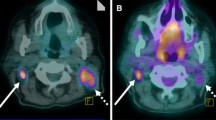

All primary tumours and more than 90% of clinically suspected locoregional metastases could be delineated. In total, 24 lesions (15 NSCLC and 9 HNC) were defined. A small subset of lesions (5/24) required manual intervention during delineation (Fig. 1). Full kinetic analysis was possible for 23 lesions; blood analyses failed in one patient. The median lesion size (threshold defined PET volume) was 8.2 cm3 (range 1.7–86.1 cm3), the median NLR3k-derived Ki was 0.047 ml·min−1·ml−1 (range 0.021–0.120 ml·min−1·ml−1), the median Patlak-derived Ki was 0.037 ml·min−1·ml−1 (range 0.017–0.074 ml·min-1·ml-1), the median SUV41% was 3.3 (range 1.3–6.4) and the median SUVmax was 4.8 (range 2.4–9.3). The 3k model provided better fits than the 4k model in 26 (57%) and 28 (61%) of 46 measured lesions according to Akaike and Schwarz criteria, respectively. In other words, the majority of the data were best fitted with the 3k model. Visual check of the TACs revealed good fits for all lesions.